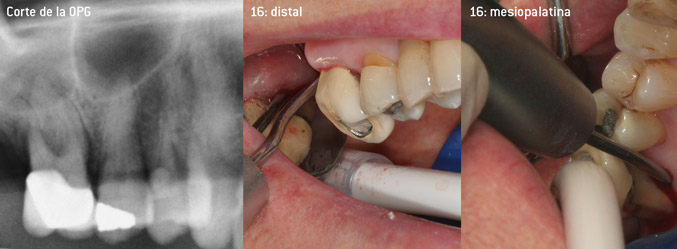

Como precursores del desarrollo de la nueva punta diamantada 3AP para eliminadores de sarro neumáticos, los dos odontólogos constataron que era necesario limitar el uso de las puntas diamantadas que se estaban comercializando hasta la fecha, sobre todo durante los tratamientos de furcaciones o en bolsas interradiculares estrechas. Además, esto debe llevarse a la práctica independientemente de si se trata de un procedimiento no quirúrgico (figura 2) o de un procedimiento quirúrgico (figura 3).

Desbridamiento abierto de las furcaciones de las piezas 16 y 17

Fig. 3: Desbridamiento abierto de las furcaciones de las piezas 16 y 17 con pérdida de adherencia avanzada